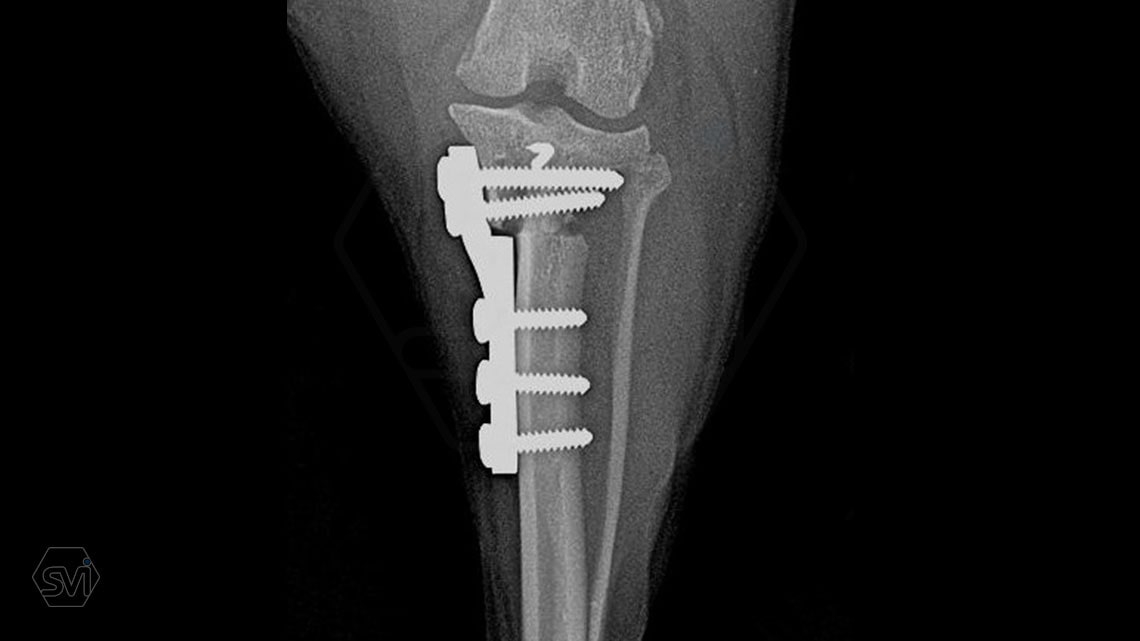

Introducing the TPLO-M „terraced” plate family from Smartvetimplants.com

In small dogs, medial patella luxation (MPL) and the rupture of anterior cruciate ligament (RACL) often occur simultaneously. During the surgical procedure, the joint must be stabilized and the patella fixed in the middle axis at the same time.

The solution of Smatvetimplants is the TPLO-M plate family with terrace:

Between October 2020 and December 2021, we performed 19 TPLO-M surgeries at the Animal Hospital in Nyíregyháza,: 16 times used the mini (2.0 R12) and 3 times the small (2,4 R15) TPLO-M plate.

The experience is very encouraging, we find the system and plates suitable for the simultaneous treatment of MPL and RACL. ( in case of 4/4 pat. lux. also). We will back soon with details.